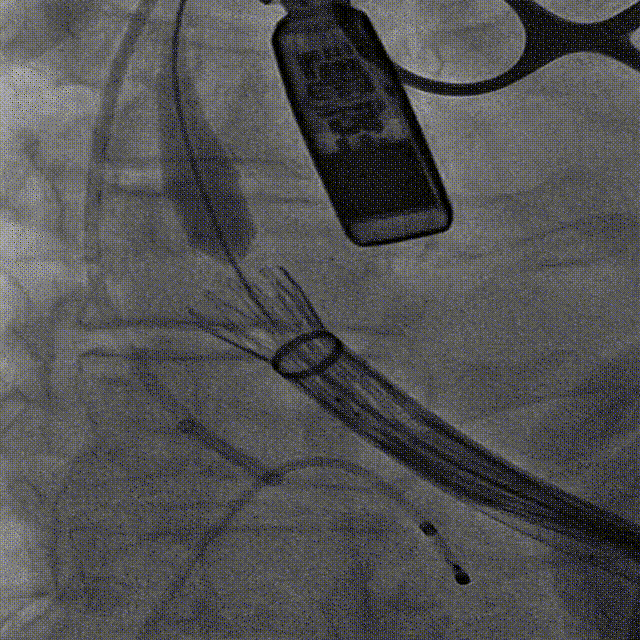

主动脉根部造影

TA32瓣膜,第一次释放

造影观察,瓣膜较深,可见瓣周漏

瓣架打平造影,瓣膜位置偏深,回收